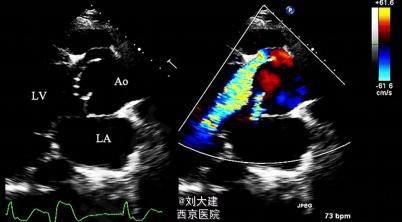

体格检查在左侧第三肋间闻及 3/6 级的「拉锯样」杂音。胸片检查发现心影增大,心电图显示完全左束支传导阻滞伴频发室早。经胸壁心脏超声显示左心室极度扩大,左心室舒张末期容积为 472 ml,射血分数(EF)为 20%。

心脏超声和多层 CT 血管造影发现一隧道样结构,伴收缩期顺流和舒张期逆流,该结构起源于主动脉根部,刚好位于扩张的主动脉窦水平之上,缠绕左下进入左心室。最终诊断为 II 型 ALVT(以隧道结构的心脏外主动脉壁动脉瘤伴或不伴瓣膜变形为特征),术中探查后明确诊断,手术关闭隧道后患者表现良好。